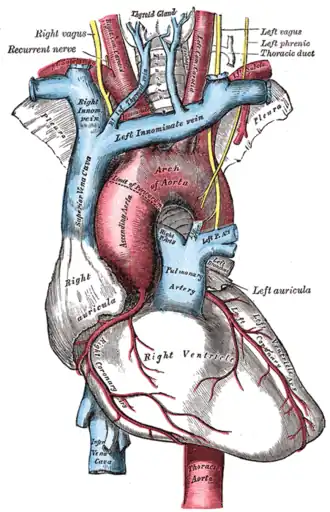

The arch of the aorta, and its branches

The arch of the aorta, and its branches -